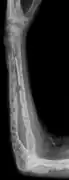

The diagnostic examination of a person with suspected multiple myeloma typically includes a skeletal survey. This is a series of X-rays of the skull, axial skeleton, and proximal long bones. Myeloma activity sometimes appears as "lytic lesions" (with local disappearance of normal bone due to resorption) or as "punched-out lesions" on the skull X-ray ("raindrop skull"). Lesions may also be sclerotic, which is seen as radiodense.[70] Overall, the radiodensity of myeloma is between −30 and 120 Hounsfield units (HU).[71] Magnetic resonance imaging is more sensitive than simple X-rays in the detection of lytic lesions, and may supersede a skeletal survey, especially when vertebral disease is suspected. Occasionally, a CT scan is performed to measure the size of soft-tissue plasmacytomas. Nuclear Medicine Bone scans are typically not of any additional value in the workup of people with myeloma (no new bone formation; lytic lesions not well visualized on nuclear bone scan).

- X-ray of the forearm, with lytic lesions

- Humerus with multiple myeloma lesions

- Same humerus before, with just subtle lesions